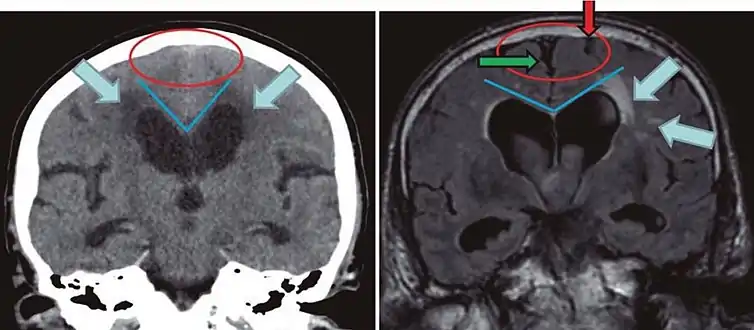

CT and MRI are most commonly used to observe the brain for cerebral atrophy. A CT scan takes cross sectional images of the brain using X-rays, while an MRI uses a magnetic field. With both measures, multiple images can be compared to see if there is a loss in brain volume over time.[20]

Cerebral atrophy can be hard to distinguish from hydrocephalus because both cerebral atrophy and hydrocephalus involve an increase in cerebrospinal fluid (CSF) volume. In cerebral atrophy, this increase in CSF volume comes as a result of the decrease in cortical volume. In hydrocephalus, the increase in volume happens due to the CSF itself.[20]

| Normal pressure hydrocephalus | Brain atrophy | |

|---|---|---|

| Preferable projection | Coronal plane at the level of the posterior commissure of the brain. | |

| Modality in this example | CT | MRI |

| CSF spaces over the convexity near the vertex (red ellipse | Narrowed convexity ("tight convexity") as well as medial cisterns | Widened vertex (red arrow) and medial cisterns (green arrow) |

| Callosal angle (blue V) | Acute angle | Obtuse angle |

| Most likely cause of leucoaraiosis (periventricular signal alterations, blue arrows |

Transependymal cerebrospinal fluid diapedesis | Vascular encephalopathy, in this case suggested by unilateral occurrence |